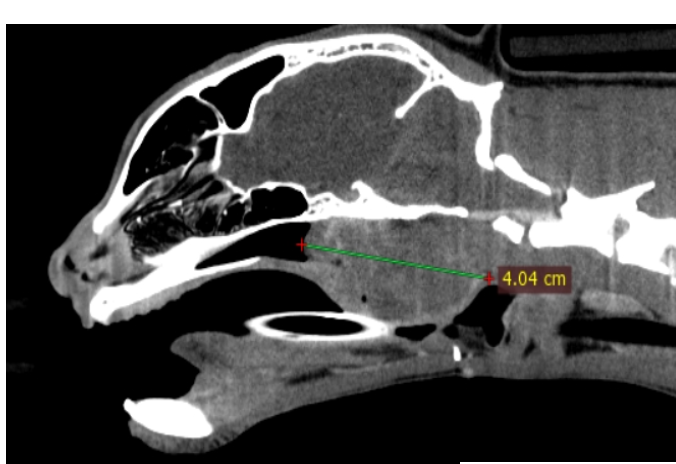

CT (Computed Tomography)

There are many indications for CT scan in animals - such as further evaluation of the nasal cavity, checking for ectopic ureters, finding abnormal vessels, etc.

Dog with normal nasal cavity and sinuses

Cat with a nasal mass - biopsy confirmed lymphoma

Another cat with nasal lymphoma

Cat with chronic rhinitis and sinusitis